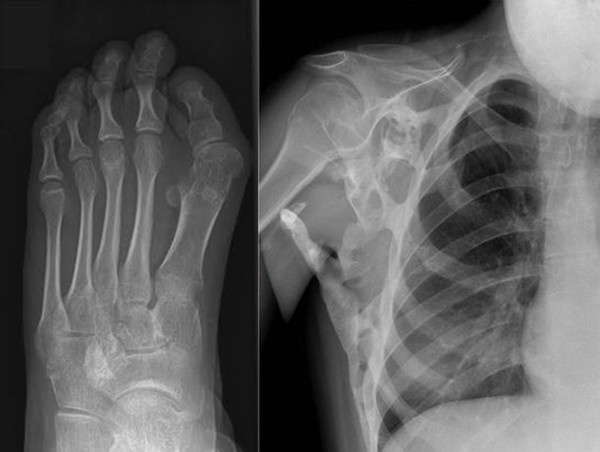

Cụ bà Đoàn Thị Ngôn (97 tuổi, Nam Định) bị mọc một cái sừng dài hơn 20 cm ở đầu gối trông như sừng trâu khiến cụ luôn đau nhức.

Cách đây 8 năm, tại xã Phúc Thọ (huyện Lâm Hà, Lâm Đồng), một người đàn ông khỏe mạnh bỗng dưng mắc căn bệnh lạ khiến chân tay hóa sừng không làm được việc gì.

Bàn chân dài quắt queo, đôi tay với những ngón dài thuồn thuột, ngoằn ngoèo, toàn thân nổi lên những mảng vảy trắng bợt bong tróc không ngớt.

Căn bệnh khiến chân tay anh Nguyễn Đình Nhi và con trai Nguyễn Đình Vương (trú xã Tam Anh Bắc, Núi Thành, Quảng Nam) co quắp, toàn thân nổi như vảy rắn, chảy máu.

Căn bệnh lạ đã hành hạ anh Nhi và cháu Vương nhiều năm trời, khiến ai cũng không muốn tiếp xúc vì sợ bị... lây.

Một nữ sinh sống tại Birmingham, Anh Quốc, mắc căn bệnh lạ khiến một bộ xương thứ hai phát triển bên trong cơ thể cô.